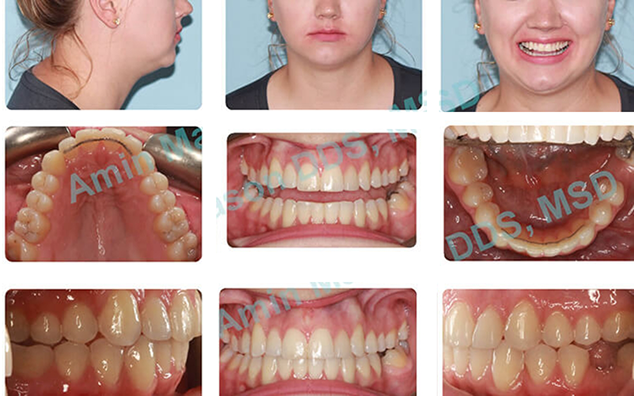

Case 1

Adult female, anterior and posterior crossbite, crowded arches, and worn dentition.

Treatment: Patient was treated with Invisalign clear aligners only.